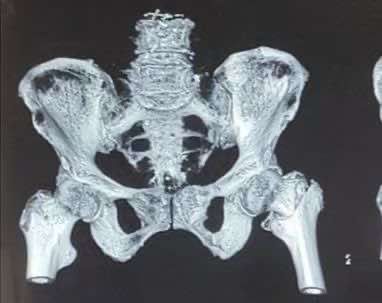

患者戴奶奶,100岁,因行走时不慎滑倒,左侧髋部疼痛难耐,休息后疼痛无好转被家人送入铜川矿务局中心医院骨二科治疗。检查结果显示患者左股骨转子间骨折,医生建议入院手术治疗。

通常股骨转子间骨折都是优先考虑手术治疗。陕健医铜川矿务局中心医院副院长贾玉龙和骨二科主任杨坤看过戴奶奶的病历后表示,可以为戴奶奶进行手术!“医院骨二科在给高龄患者手术方面积累了丰富的经验,治疗高龄患者尽可能缩短手术时间,术中减少创伤,而且麻醉时间等都不能过长。”副院长贾玉龙介绍说。

万事俱备,东风徐来。骨二科手术团队在副院长贾玉龙、主任杨坤带领团队在手麻科的配合下,为戴老太太行粗隆间骨折微创手术,3个切口共5cm,历时20分钟,手术顺利完成。